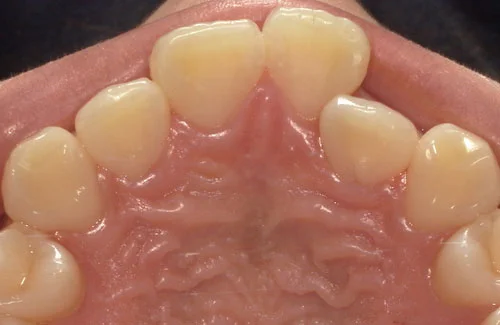

- 症例1

費用 396,000円(税込)

治療期間 6ヶ月

治療内容 マウスピースを用いた歯列矯正

追加処置 IPR

※保険適用外の自由診療となります。